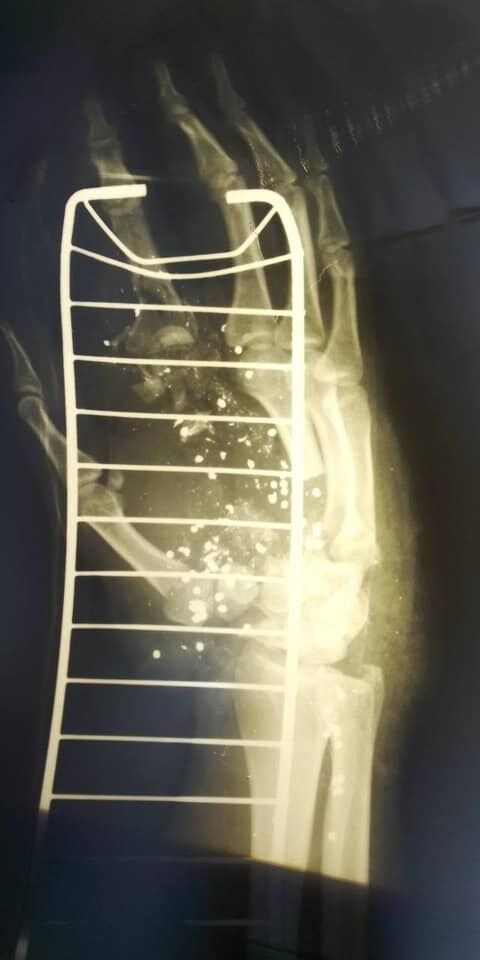

В ходе стрельбы в Голосеевском районе Киева 7 июля пострадал 27-летний патрульный Сергей Василенко, который работает в НПУ с 2019 года. Мужчина получил тяжелую травму руки, конечность пытаются спасти врачи.

"Сейчас за его руку борются лучшие специалисты больницы Шалимова и он уже перенес одну операцию. Предоставляется максимальная помощь по лечению и реабилитации, но процесс будет долгим и сложным. И конечно, результат пока неизвестен", – рассказал полицейский.

В свою очередь заместитель министра внутренних дел Антон Геращенко уточнил: по прогнозу медиков, если не будет осложнений и нагноений, есть шанс, что через полгода пальцы на травмированной руке полицейского снова будут работать.

"Надеемся что все будет хорошо, хотя конечно рука Сергея уже никогда не будет такой, как прежде", – написал Геращенко в своем блоге, который был опубликован.